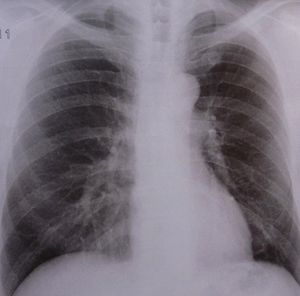

Röntgenbild: Armut senkt Überlebenschancen (Foto: pixelio.de, Dieter Schütz) |